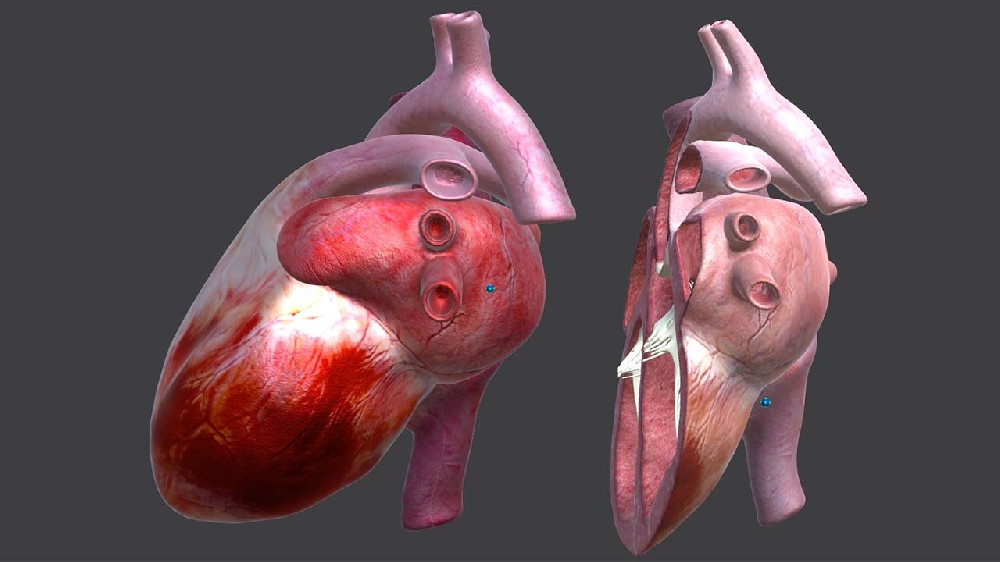

增強現(xiàn)實(Augmented Reality,AR)技(jì)術(shù)是(shì)一( yī)種将虛拟信息與真實世界巧妙融合的(de)技(jì)術(shù),廣泛運用(yòng)了(le)多(duō)媒體(tǐ)、三維建模、實時(shí)跟蹤及注冊、智能(néng)交互、傳感等多(↑duō)種技(jì)術(shù)手段,将計(jì)算(suàn)機(jī)生(shēng)成的(de)文(wén)字、圖像、三維模型、音(yīn)樂(yuè)、視(shì)頻(pín)等虛拟信息模拟仿真後,應用(yòng)到(dào)真實世界中,兩種信息互為(wè i)補充,從(cóng)而實現(xiàn)對(duì)真實世界的(de)“增強”。